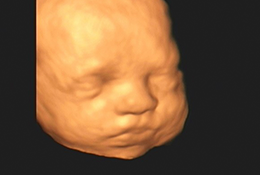

Com alta tecnologia realizamos diversos tipos de ultrassonografias: Obstétrica, Obstétrica com Doppler, Morfológica, 4D, Transvaginal, Transvaginal para pesquisa de Endometriose, Abdominal, Mamas, Tireoide e outros.